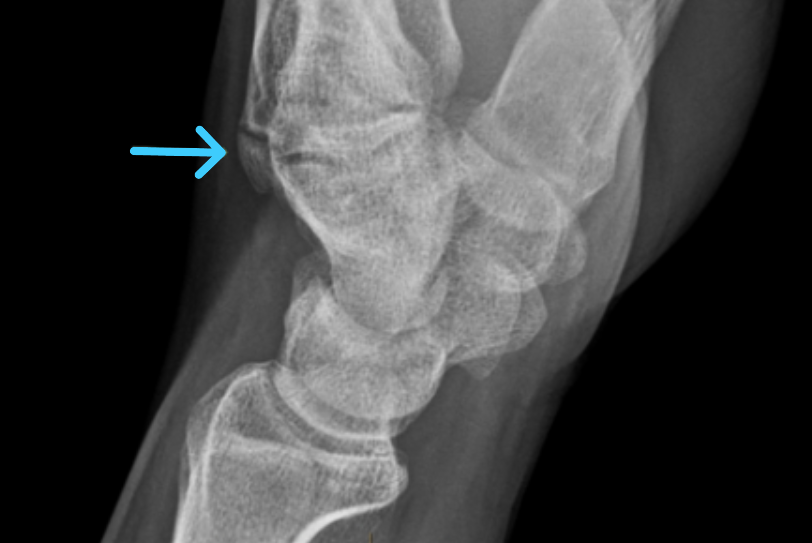

영상의학 검사: X-ray, CT, MRI로 단단한 뼈 돌출 확인 및 감별